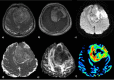

The role of conventional Magnetic Resonance Imaging (MRI) in the detection of cerebral tumors has been well established. However its excellent soft tissue visualization and variety of imaging sequences are in many cases non-specific for the assessment of brain tumor grading. Hence, advanced MRI techniques, like Diffusion-Weighted Imaging (DWI), Diffusion Tensor Imaging (DTI) and Dynamic-Susceptibility Contrast Imaging (DSCI), which are based on different contrast principles, have been used in the clinical routine to improve diagnostic accuracy. The variety of quantitative information derived from these techniques provides significant structural and functional information in a cellular level, highlighting aspects of the underlying brain pathophysiology. The present work, reviews physical principles and recent results obtained using DWI/DTI and DSCI, in tumor characterization and grading of the most common cerebral neoplasms, and discusses how the available MR quantitative data can be utilized through advanced methods of analysis, in order to optimize clinical decision making.